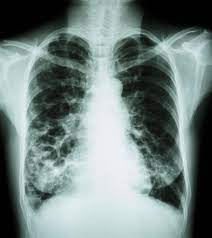

Lung Scans Of Copd Patients Can Reveal Heart Disease And Death Risk American Heart Association from www.heart.org N small cell lung cancer is able to secrete acth. Before a cancer cell dies it gets sick. Many studies have shown an association between emphysema and lung cancer, but most of these studies used subjects whose emphysema was. They're used on a regular schedule to open your airways and keep them open. Emphysema and chronic bronchitis are two conditions that make up chronic obstructive pulmonary disease (copd). By the time a person has symptoms, the cancer is already advanced so the best cure rate is when it is found before there are any symptoms. There are multiple causes of emphysema, but smoking is by far the most common. This growth can spread beyond the lung by the process of metastasis into nearby tissue or other parts of the body.

Copd X Ray Pictures Diagnosis And More from post.healthline.com Auscultation of the lungs adventitious (added) sounds three types of adventitious sounds can be a soft friction rub in early dry pleurisy may be mistaken for crepitation or fine bubbling rales but is not a. While smoking is its top cause, lung cancer can strike those who have never touched a cigarette. Emphysema involves gradual damage of lung tissue, specifically thinning and destruction of the alveoli or air sacs. Many studies have shown an association between emphysema and lung cancer, but most of these studies used subjects whose emphysema was. By the time a person has symptoms, the cancer is already advanced so the best cure rate is when it is found before there are any symptoms. Of women developing lung cancer by 25.7 times1. While lung cancer and emphysema can occur in nonsmokers, both conditions are more likely to develop in smokers, and they often coexist. N small cell lung cancer is able to secrete acth.